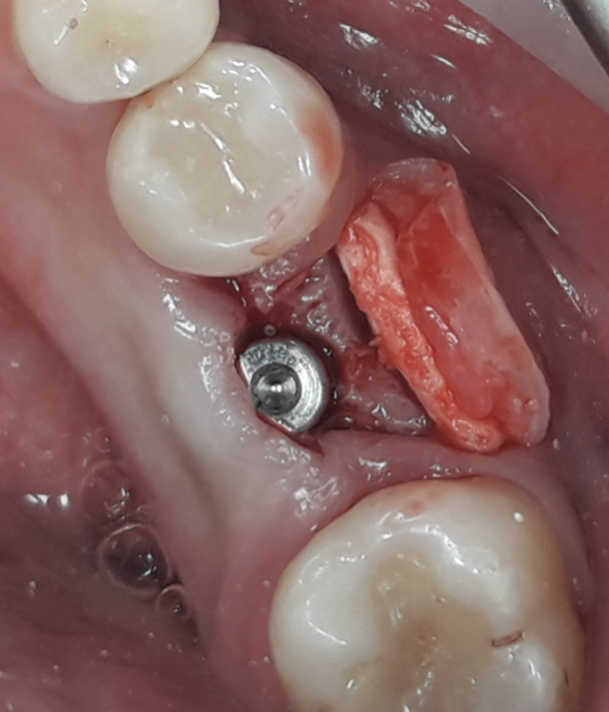

La tecnica denominata M.T.G. (Matrix Tissue Graft) si basa sull’utilizzo di una particolare matrice dermica acellulare riassorbibile di origine suina caratterizzata da un elevata consistenza e stabilità volumetrica che viene posizionata al di sotto del lembo muco periostale eseguito a spessore totale, in contatto con la cresta ossea. La stabilizzazione della matrice avviene senza mezzi di fissazione o in casi limitati mediante l’ausilio di una sutura riassorbibile con cui ancorare la matrice al lembo mucoperiosteo.

Nello studio sono stati inclusi 20 pazienti (12 donne e 8 uomini) di età compresa tra i 28 e i 65 anni, con edentulia singola e conseguente deficit vestibolare dei tessuti molli. La matrice dermica a elevata consistenza è stata opportunamente ritagliata mediante forbici e lama ed è stata posizionata al di sotto del lembo muco periostale allestito con approccio a spessore totale, vestibolarmente alla cresta ossea in cui è stato posizionato contestualmente un impianto endosseo osteointegrabile. Non si è utilizzato alcun ausilio di fissazione per la matrice dermica che è stata stabilizzata dal solo lembo di accesso ribaltato su di essa e suturato, mediante punti staccati semplici, al lembo linguale.

La tecnica M.T.G. può considerarsi una tecnica predicibile nell’aumento dei volumetrico dei tessuti molli perimplantari al pari dell’innesto connettivale o epitelio connettivale. L’utilizzo di una matrice dermica a elevata consistenza applicata con questa tecnica offre ulteriori vantaggi rispetto alla tecnica di innesto connettivale. Oltre a ridursi l’invasività per il paziente non richiedendo un sito donatore, la matrice può essere disponibile in quantità difficilmente reperibili con un innesto connettivale. La matrice dermica utilizzata inoltre può essere lasciata parzialmente esposta nel cavo orale ed è facilmente modellabile addirittura in una fase preparatoria di progettazione dell’intervento chirurgico.